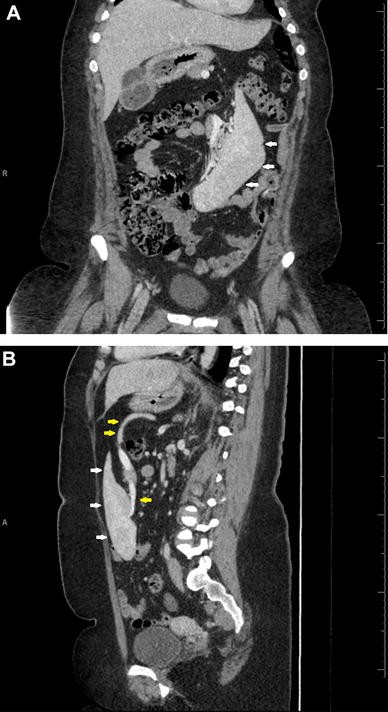

Spleen Quadrant / Ectopic Spleen Presenting As Pelvic Mass / Wandering spleen is a rare condition in which the spleen migrates from its usual anatomical position enlarged spleen, with minimal or no enhancement.. On plain films, a mass was seen in the left upper quadrant, and on computed tomography (ct), a spleen with a whorled pedicle suggesting torsion was identified. It is made up of two different types of tissue. Chapter 8 left upper quadrant pain sheryl e. Normally, even if you press hard. Most splenic lesions are detected incidentally, posing a in this group of focal splenic lesions, patients present with left upper quadrant pain due to mass effect and stretching of the splenic capsule.